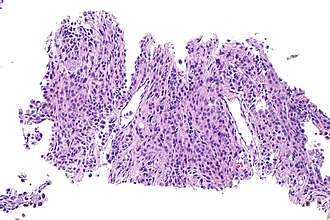

| Caption = Pneumocytoma. [[H&E stain]]. (WC/Nephron) | |||

Pneumocytoma. H&E stain. (WC/Nephron) | |

| LM | mixed cell population, variable architecture (papillary, sclerotic, solid, hemorrhagic), +/-granulomas |

| LM DDx | carcinoid tumour, papillary pattern lung adenocarcinoma, metastatic papillary thyroid carcinoma |

| IHC | TTF-1 +ve, Ki-67 +ve membranous pattern, PR +ve, CD56 -ve, CD34 -ve |

Microscopic

Features:[7]

- Mixed cell population.

- Variable architecture:

- Papillary.

- Sclerotic.

- Solid.

- Hemorrhagic.

- +/-Granulomas.

The sections show lung with thickened alveolar walls containing bland appearing cells with round/oval nuclei without conspicuous nucleoli. Necrosis is absent.